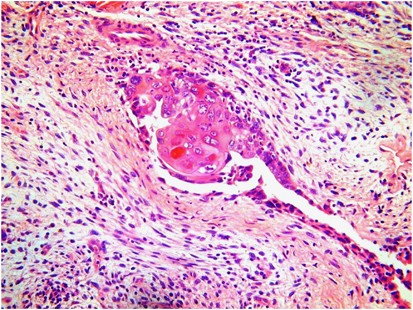

A histological diagnosis of carcinosarcoma depends on identifying high-grade malignant epithelial and mesenchymal components typically showing a sharp demarcation between both, although occasionally this demarcation may be blurred (Figure 1). The epithelial element may include serous, grade 3 endometrioid, clear cell and undifferentiated carcinoma in order of frequency. Admixtures may be seen and typing of the epithelial component may be difficult; in some cases, a hybrid morphology (with features of serous and endometrioid carcinoma) or a malignant squamous component is present (Figure 2), which may be a clue to the diagnosis. The mesenchymal component can be homologous or heterologous. The former is typically a high-grade sarcoma, NOS and eosinophilic hyaline globules are frequently noted. If heterologous elements are present, then rhabdomyoblasts or malignant cartilage is the most common. Osteosarcomatous and liposarcomatous differentiation may rarely occur (Figure 3). On occasion, carcinosarcomas are associated with a component of primitive neuroectodermal tumour (PNET); in such cases, markers such as neurofilament, glial fibrillary acidic protein (GFAP) and synaptophysin may be useful in highlighting this component, which is more analogous to a central than a peripheral PNET without EWSR1 gene rearrangement.9 Occasional examples of a yolk sac tumour component and melanocytic differentiation have also been reported.10, 11

The relative proportions of epithelial and mesenchymal components vary widely; thus, extensive sampling in an undifferentiated sarcoma or pleomorphic rhabdomyosarcoma may reveal areas diagnostic of carcinosarcoma. Uncommonly, carcinosarcomas have a low-power growth pattern, which mimics an adenosarcoma (Figure 4); however, this is usually a focal finding, there is no stromal condensation, and the epithelium and the stroma are overtly malignant at high-power magnification.